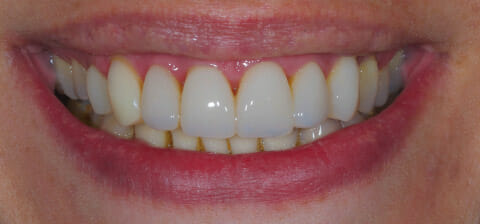

Una volta curata la parodontite e ripristinata la funzionalità corretta della bocca sono state eseguite anche la terapia ortodontica fissa e la terapia estetica.

Il risultato è stato il salvataggio di elementi a rischio estrazione e il ripristino sia funzionale che estetico della bocca della paziente, che ha potuto ritrovare la fiducia nel suo sorriso.